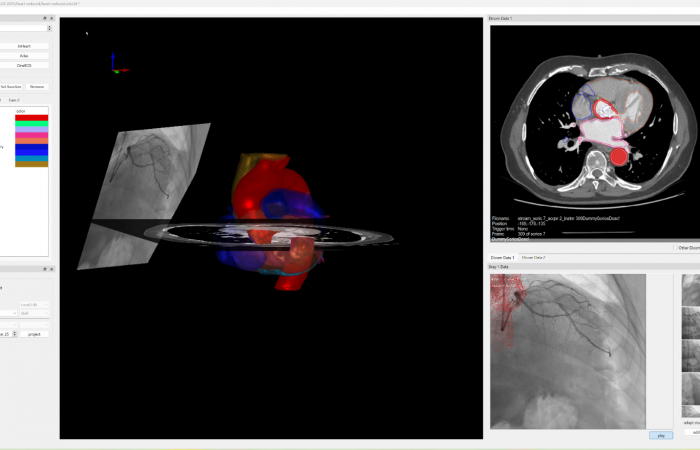

Pracownia Funkcjonalnego i Wirtualnego Medycznego Obrazowania 3D (Pracownia 3D-FM) funkcjonuje w strukturze Zakładu Diagnostyki Obrazowej Szpitala Uniwersyteckiego w Krakowie pod kierownictwem Prof. dr hab. Tadeusza Popieli. Jej celem jest opracowanie i wdrożenie innowacyjnych metod przetwarzania oraz analizy sygnałów i obrazów medycznych, w tym wykorzystanie technologii rzeczywistości wirtualnej oraz metod obrazowania funkcjonalnego. Rozwiązania te wspierają przedoperacyjne planowanie, monitorowanie procedur medycznych oraz wzbogacają proces diagnostyczny o nowe formy wizualizacji danych medycznych.

Zakres działalności

Pracownia 3D-FM zajmuje się m.in. następującymi obszarami:

- Tworzeniem modeli 3D do celów przedoperacyjnego planowania oraz wizualizacji diagnostycznej.

- Rozwojem rozwiązań programowych do obrazowania medycznego.

- Integracją urządzeń i systemów diagnostycznych (PACS, RIS, HIS, OIS) z infrastrukturą szpitalną, umożliwiającą efektywne zarządzanie danymi obrazowymi i funkcjonalnymi.

- Oceną jakości i poprawności danych medycznych w celach wizualizacji przestrzennych oraz optymalizacją protokołów akwizycji i konfiguracją urządzeń do tych celów.

- Współpracą z jednostkami organizacyjnymi Szpitala Uniwersyteckiego oraz partnerami zewnętrznymi.

- Poszukiwaniem nowych możliwości rozwoju w zakresie funkcjonalnego i wirtualnego obrazowania medycznego 3D.

- Analizą biostatystyczną danych medycznych i edukacja w zakresie nowych technologii.

Obszary badawcze

- Obrazowanie Medyczne 3D

- Segmentacja i analiza danych DICOM

- Rekonstrukcja danych medycznych

- Technologie immersyjne (mieszana, rozszerzona i wirtualna rzeczywistość)

- Obrazowanie funkcjonalne

- Analiza surowych danych biologicznych

- Analiza sygnałów z czujników (np. kamera 3D, przenośny analizator oddechu „Sniffer”)

- Elektrokardiograficzne obrazowanie 3D (ECGI)

- Modelowanie fizjologiczne

- Analiza sygnałów czasowych, w tym EKG

- Projektowanie i konstrukcja mechaniczna

- Analiza danych medycznych i edukacja

- Programowanie i metody statystyczne (w tym AI) w analizie danych medycznych

- Zarządzanie danymi

- Opracowanie kursów edukacyjnych dla studentów, lekarzy, rezydentów i doktorantów

- System zintegrowanych kwalifikacji

Pracownia Funkcjonalnego i Wirtualnego Medycznego Obrazowania 3D łączy nowoczesne technologie z praktycznym zastosowaniem w diagnostyce i terapii. Dzięki interdyscyplinarnej współpracy oraz zaawansowanym narzędziom badawczym dążymy do podnoszenia standardów opieki medycznej w Szpitalu Uniwersyteckim w Krakowie.